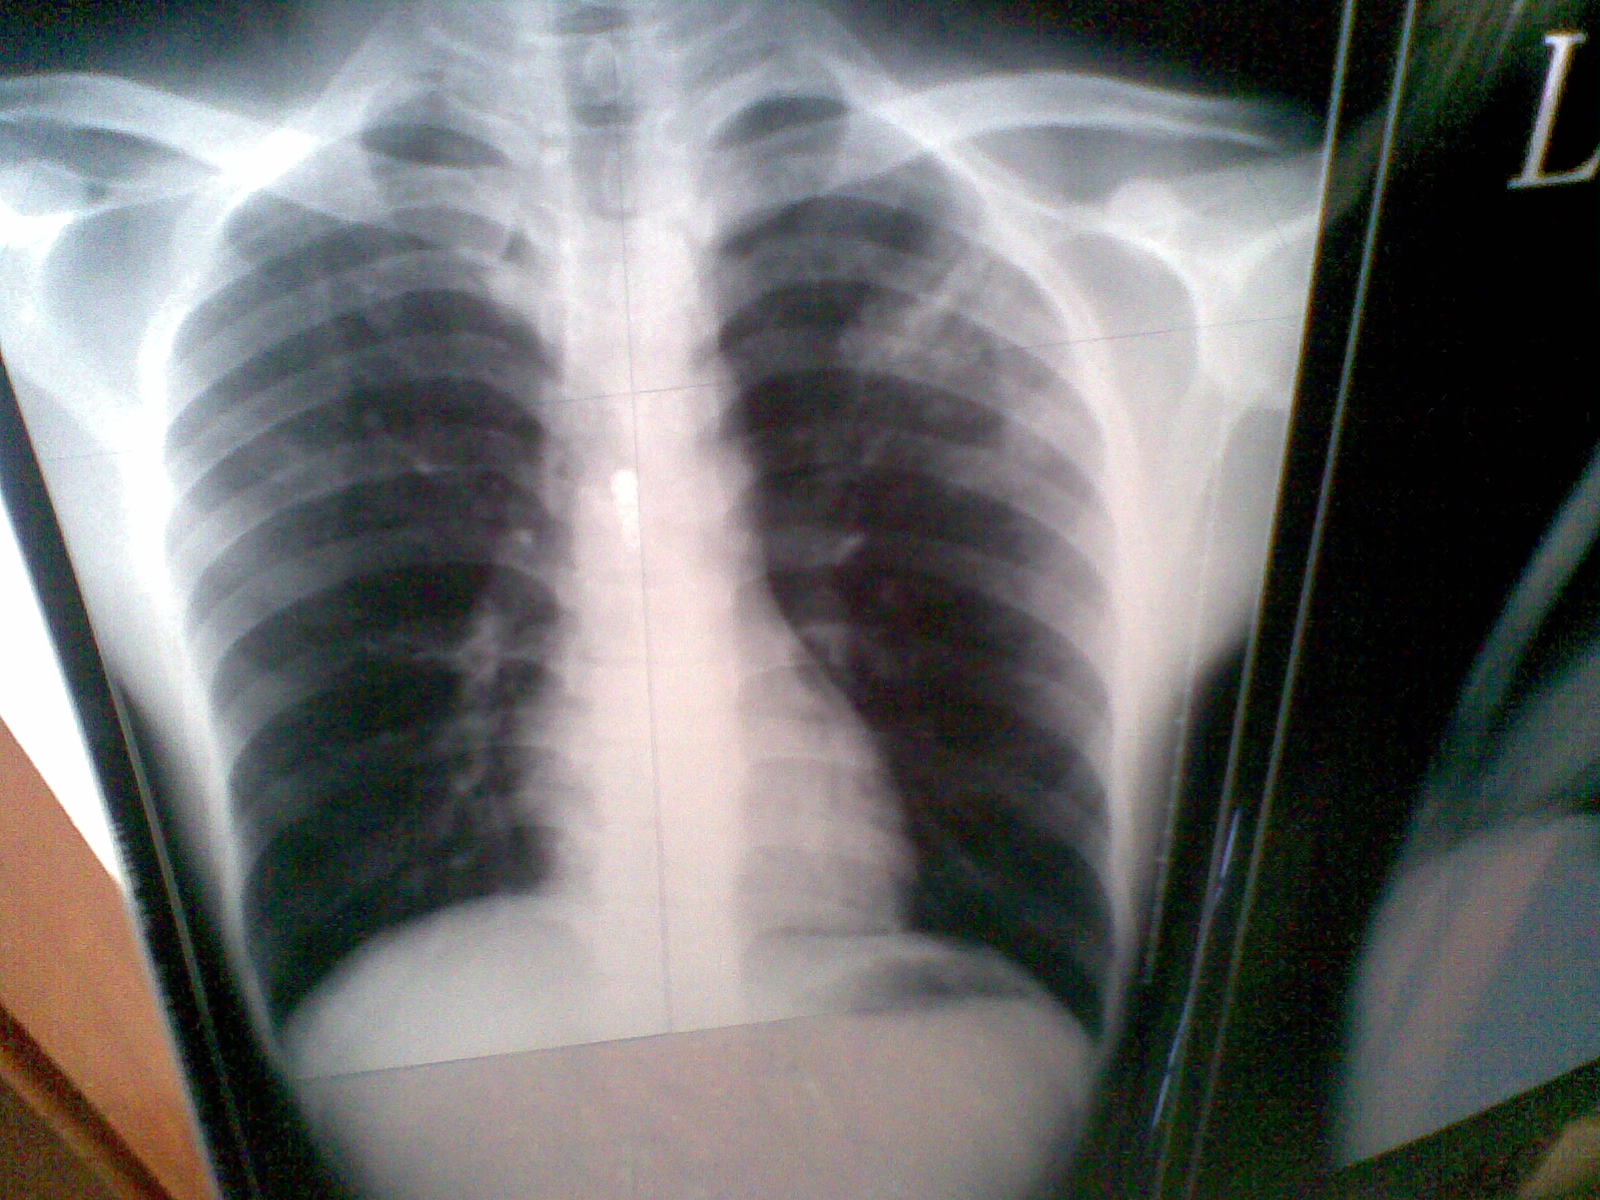

浸润性肺结核图片

因为工作要去体检 结果检查说有左上浸润型肺结核.

肺渗出(浸润)性病变:浸润型肺结核.

浸润性肺结核的影像学特征

浸润性肺结核表现最多样,最突出的表现就是会产生典型的结核结节及